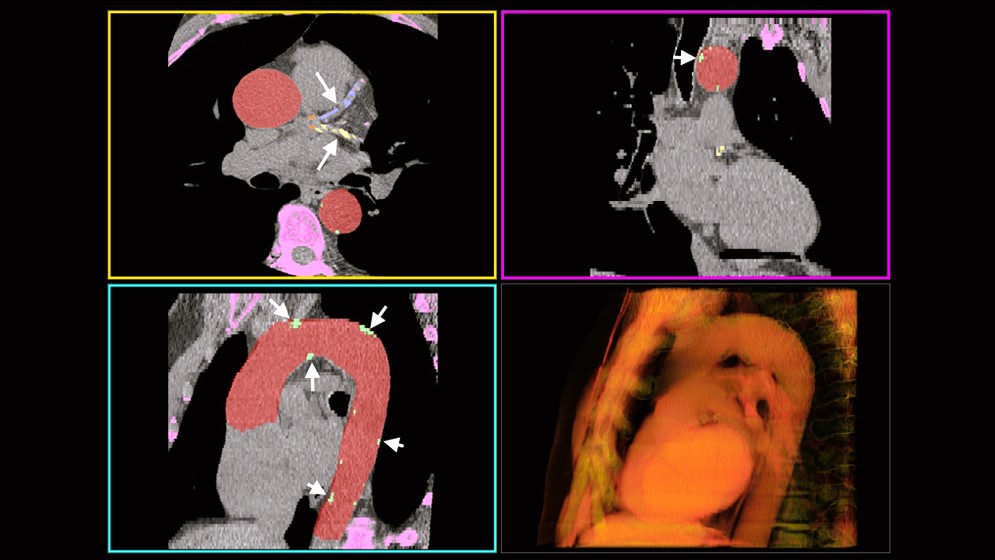

El calcio vascular se observa en las tomografías como manchas blancas que aparecen en los bordes de las paredes arteriales. Para medirlo, el radiólogo utiliza generalmente un software que le permite explorar plano a plano el corazón y las arterias, resaltar los candidatos que pueden ser potenciales lesiones y luego hacer clic sobre cada uno para validarlos. «Un paciente puede tener decenas de calcificaciones y este procedimiento suele ser largo y tedioso. Nuestro proyecto consistió en entrenar un software para que primero aprenda a reconocer la aorta, donde se forman las calcificaciones, y luego busque potenciales lesiones y decida cuáles son verdaderas. En un par de minutos, el sistema de IA entrega las mediciones de calcio que a un radiólogo a veces puede llevarle entre 15 y 30 minutos», puntualiza Craiem. Y agrega: «En resumen, el sistema basado en IA permite medir automáticamente un score de calcio torácico. Como el riesgo de los eventos cardiovasculares está asociado a la cantidad de calcio en las arterias, esta herramienta automática ayuda a los cardiólogos a mejorar los tratamientos preventivos».

«En medicina lo más ético es interesarse sobre los errores del sistema y no solo sobre sus aciertos. ¿Qué sucede con ese 5% de error? ¿Cuántos pacientes son? ¿Qué consecuencias puede provocar el error de medición sobre el diagnóstico de esas personas? Nuestro sistema fue diseñado para que, en caso de cometer un error, lo haga hacia arriba. Es decir, sobrestimando la cantidad de calcio y nunca subestimando. Esto permite que, en el peor de los casos, el sistema informe un valor de calcio mayor al que corresponde y que el médico pueda evaluar y corregir la medición», explica Craiem. Y continúa: «Nuestro sistema está diseñado no solo para calcular el score de calcio e informar un número, sino para que el radiólogo pueda ver en pantalla las calcificaciones detectadas y dar su opinión sobre la detección».